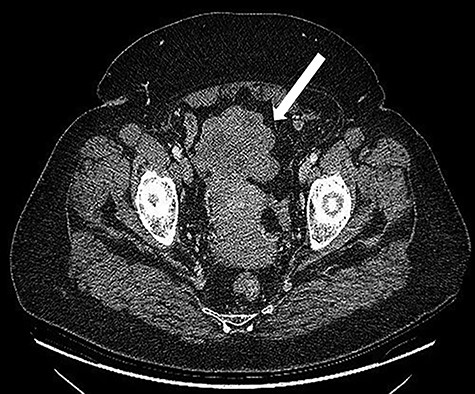

A 68-years-old woman (body mass index 35.6) was admitted with recent onset sideropenic anemia and not heart-related angina pectoris. At physical examination, a slightly mobile mass in the left iliac fossa was palpable. Carcinoembryonic antigen, carbohydrate antigen 19.9 (CA 19.9) carcinoma antigen 125 (CA 125) were normal. Upper and lower GI endoscopy were negative for any lesion. The patient was submitted for computed tomography (CT) scan, showing multiple solid density processes with colliquation areas in the abdominal cavity (Fig. 1). The greatest mass (8.0 × 5.6 cm) was located in the pelvis in close contact with the uterine fundus and the small bowel (Fig. 2). Cranially to this process, at least 20 other tumors with a diameter between 0.8 and 3.8 cm could be appreciated.

CT scan: multiple solid density processes with colliquation areas within them (white arrows) in the abdominal cavity.